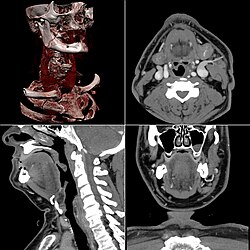

-

Craniale Computertomographie Abgebildet sind Felsenbein und Nasennebenhöhlen. Aufgrund der hohen Auflösung der Aufnahme des verwendeten 64-Zeilen-CTs sind selbst die Gehörknöchelchen erkennbar. -